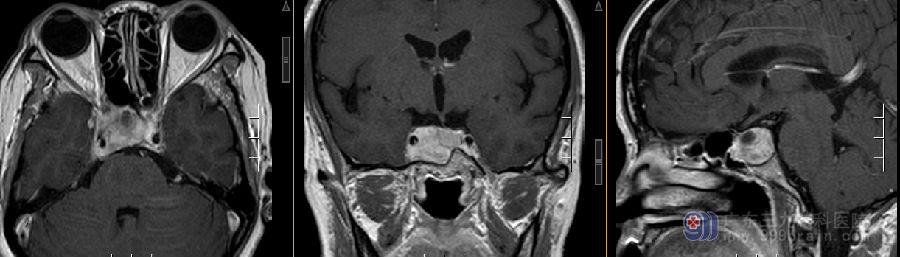

图2:术前MR示鞍区示一团块状囊实性占位性病变,实性部分呈等T1等T2信号,增强扫描明显强化,大小约27×23×19mm,病变包绕双侧颈内动脉,以右侧为著,右侧海绵窦受侵犯。垂体柄左偏,视交叉略受压。鞍底及鞍背骨质吸收变薄。